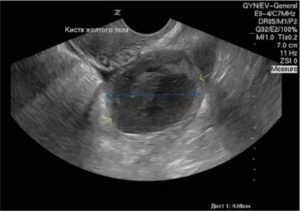

Киста – это некое образование, которое имеет внутри себя жидкость. Она формируется из ткани яичников там, где после менструации осталось желтое тело. Это происходит из-за того, что желтое тело не регрессировало до конца и осталось в тканях.

Диаметр такой кисты не больше 5-8 сантиметров, поэтому не приносит сильного беспокойства больной. Но это не значит, что такую болезнь можно упускать из виду. Наоборот, женщина должна постоянно наблюдаться у своего гинеколога.

А вот с фолликулом происходит метаморфоза: он может переродиться в кисту. Поэтому, чтобы проверить работу репродуктивной системы, могут назначить УЗИ персистенции желтого тела.

Для гинекологии этот репродуктивный процесс важен в тех случаях, когда происходят нарушения в формировании, созревании и регрессе яичникового образования. Оптимальный вариант диагностики – УЗИ, когда можно увидеть, как образуется фолликул и формируется желтое тело.

Иногда может произойти скопление жидкости внутри кистозной полости, оставшейся в том месте, где был фолликул. В этом случае возникает киста лютеинового тела с нарушением гормональной функции: гормон прогестерон в крови у женщины будет уменьшаться. Неприятное осложнение – разрыв кисты желтого тела, когда будет болеть внизу живота и возникнет нарушение менструального цикла.

На УЗИ врач увидит в яичнике кистозное образование, в крови будет понижен гормон прогестерон, тест на овуляцию будет положителен, а месячные придут раньше времени. Лечение подразумевает прием таблеток – врач назначит препарат Дюфастон для поддержания 2 фазы и возможности желанного зачатия.